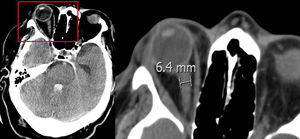

Vaina del nervio óptico: se midió el diámetro a 3 y 10 mm del globo ocular (fig. 1), los resultados se muestran en la tabla 1. No se encontró diferencia significativa entre el diámetro de la vaina del nervio óptico y la ME precoz.

La vaina del nervio óptico acumula líquido cefalorraquídeo y aumenta su diámetro en la hipertensión intracraneal. Aunque en la literatura no existe unanimidad en el lugar de la medición ni el diámetro necesario para considerar hipertensión endocraneal, algunos autores encuentran que un diámetro >5-6 mm se acompaña de un PIC >20 mmHg34,35. Nosotros medimos la vaina del nervio óptico a 3 y 10 mm del globo ocular sin encontrar una relación significativa con la evolución precoz a ME; en la medición de la vaina del nervio óptico realizada a 3 mm del globo ocular, la media encontrada del diámetro fue >5 mm en los dos grupos de pacientes (ME precoz y tardía). Algunas de las limitaciones de este estudio son su análisis retrospectivo, que analiza exclusivamente pacientes que evolucionan a ME y ser realizado en un solo centro.